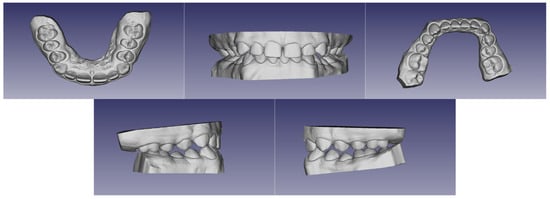

2.1. Diagnosis and Etiology

2.2. Treatment Objectives